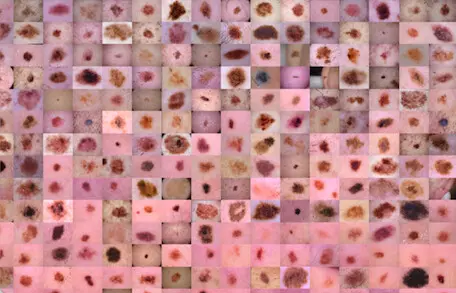

皮肤癌 MNIST:HAM10000

该数据集收集了来自不同人群的皮肤镜图像,通过不同的方式获取和存储。最终数据集包含 10015 张皮肤镜图像,可用作学术机器学习目的的训练集。案例包括色素病变领域所有重要诊断类别的代表性集合:光化性角化病和上皮内癌/鲍温氏病 (akiec)、基底细胞癌 (bcc),超过50%的病变是通过组织病理学(histo)证实的,其余病例的ground truth要么是后续检查(follow_up),要么是专家共识(consensus),要么是活体共聚焦显微镜(confocal)证实. 数据集包括具有多个图像的病变,可以通过 HAM10000_metadata 文件中的 lesion_id 列进行跟踪。